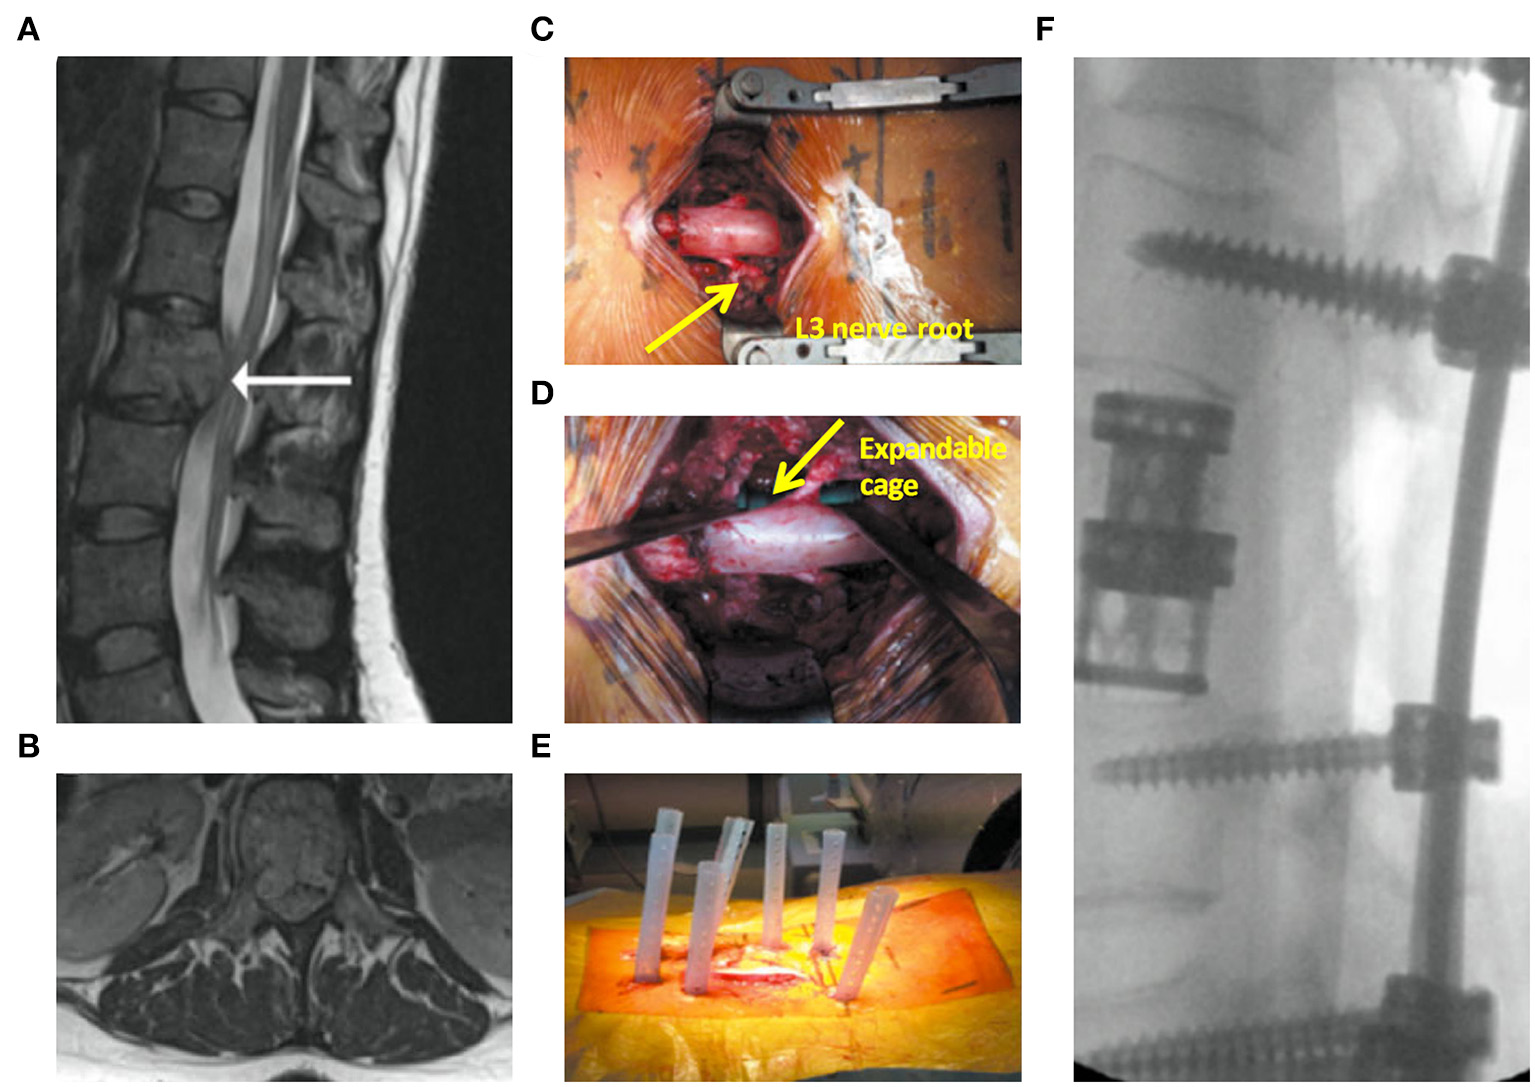

Cement augmentation techniques include percutaneous vertebroplasty (PVP) and percutaneous balloon kyphoplasty (PKP) (44). PVP is performed using high-power cement and the force of the poly-methylmethacrylate (PMMA) injection must exceed the local pressure of the cancellous bone of the vertebral body (45). Constant observation is required to prevent leakage of the bone cement. PKP was designed to raise the endplate by introducing an inflatable balloon into the compressed vertebral body (Figure 3). This is achieved by creating a low-pressure chamber filled with cement inside the vertebral body. Recently, insertion of an expandable cage has also shown satisfactory outcomes in MST patients (Figure 4) (46).

Figure 4

Expandable cage-assisted treatment (39). A 32-year-old female presented with mid-back pain and leg weakness >3 weeks. (A,B) Magnetic resonance imaging images showing a solitary L2 lesion causing compression of the circumferential cauda equina. (C) Intraoperative photograph showing a mid-line incision with circumferential decompression and vertebrectomy. Decompressed L3 nerve roots are displayed (arrow). (D) Intraoperative photograph showing expandable cage (arrow)-assisted reconstruction of the vertebral body. (E) Intraoperative photograph showing a mid-line wound closure and percutaneous fixation two levels above and below the vertebrectomy. (F) Postoperative radiograph.